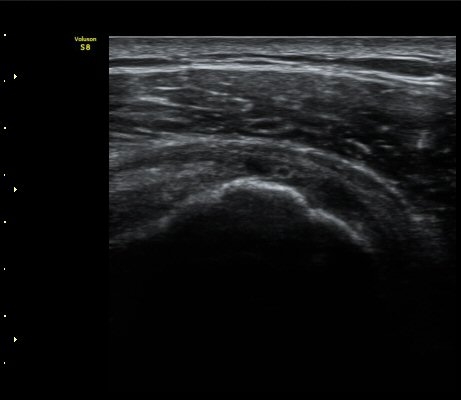

À̵ιڱ٠Ⱦ´Ü¸é°Ë»ç¿¡¼­ Á¤¸Æ³¶ÀÇ ºÎÁ¾ÀÌ °üÂûµÊ(±×¸² 1).